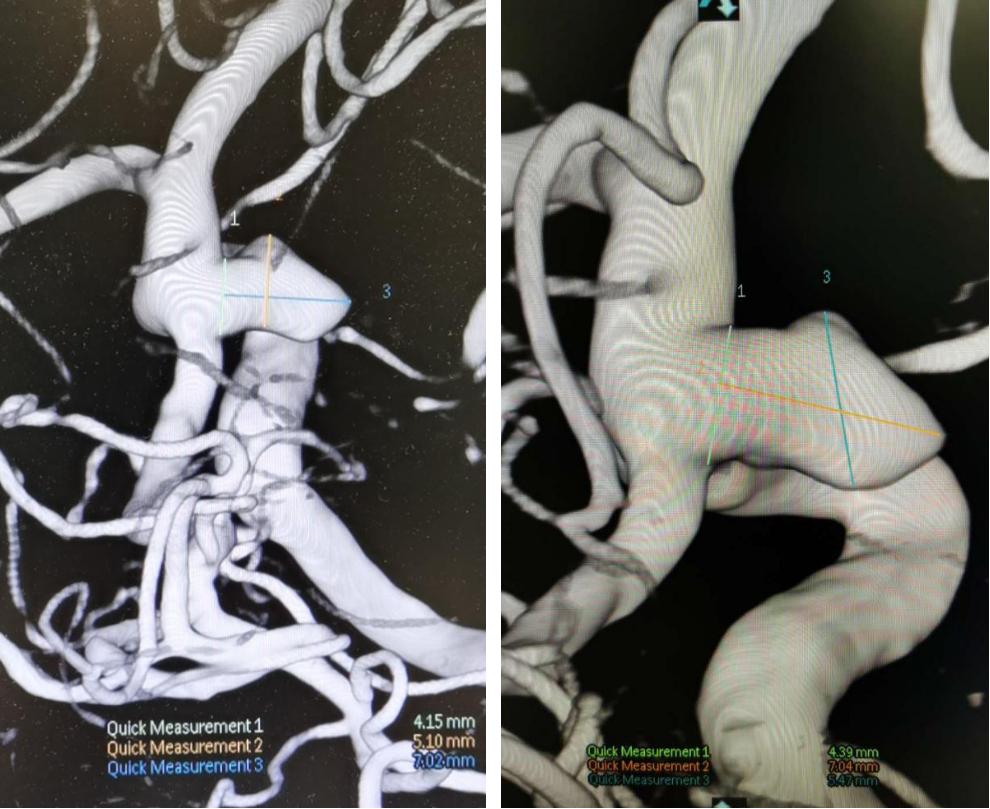

颈眼动脉多发动脉瘤的密网支架治疗

图片尺寸1080x456